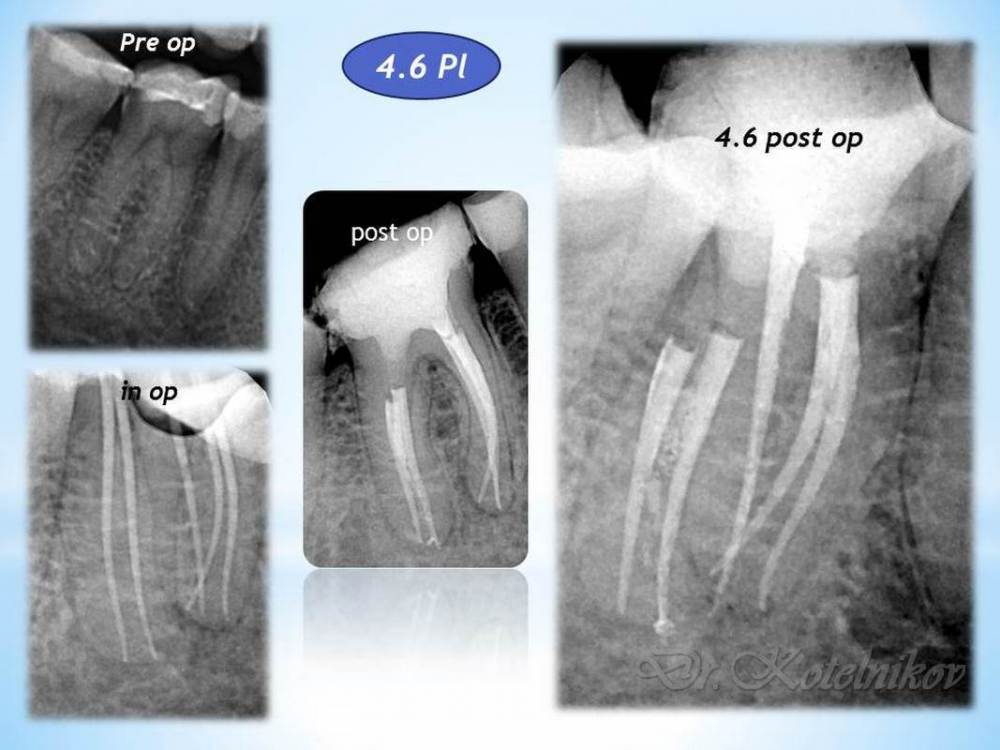

Ico Опубликовано 5 апреля, 2022 Автор Поделиться Опубликовано 5 апреля, 2022 Обострение хронического периодонтита зуб 36. После первичного эндо пропущен ДБ канал,зуб был восстановлен циркониевой вкв + циркон коронка.На пропИл до устья ушло 5 боров.Мед мех стандартный 40к+F1,паковка гибрид с Эйчем.2 визита по 2 и 1.5 часа. 3 1 Ссылка на комментарий